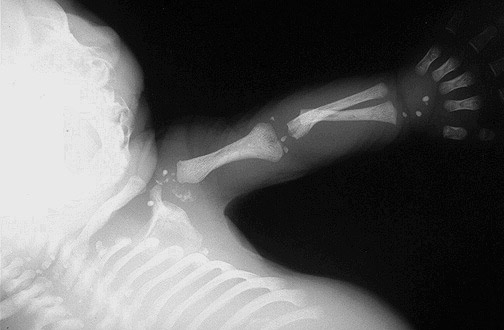

This is a case of chondrodysplasia punctata in a stillborn fetus. Note the small punctate bright areas adjacent to the ends of long bones.